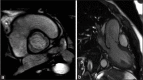

Figure 5

Aortic magnetic resonance in uncomplicated type 1 BAV. Aortic short-axis view (a), and long-axis (b) with mild eccentric regurgitation jet